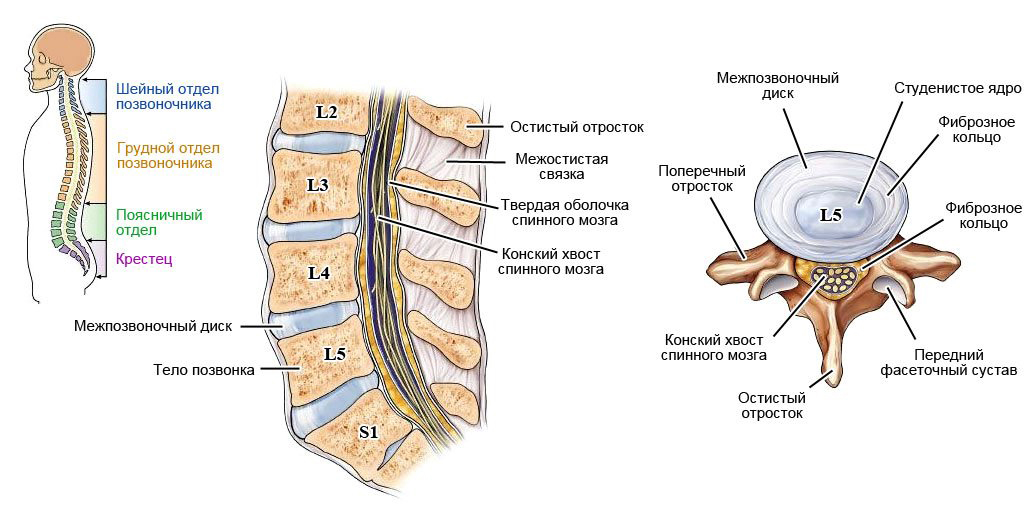

Позвонок Th10: анатомия и фото медицинских иллюстраций